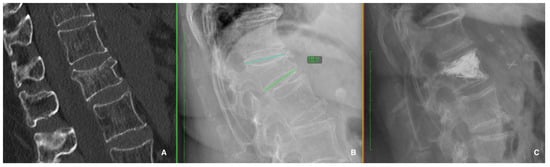

- Sugita, M.; Watanabe, N.; Mikami, Y.; Hase, H.; Kubo, T. Classification of vertebral compression fractures in the osteopo-rotic spine. J. Spinal Disord. Tech. 2005, 18, 376–381. [Google Scholar] [CrossRef] [PubMed]

- Genant, H.K.; Wu, C.Y.; Van Kuijk, C.; Nevitt, M.C. Vertebral fracture assessment using a semiquantitative technique. J. Bone Min. Res. 1993, 8, 1137–1148. [Google Scholar] [CrossRef]

- Schnake, K.J.; Blattert, T.R.; Hahn, P.; Franck, A.; Hartmann, F.; Ullrich, B.; Verheyden, A.; Mörk, S.; Zimmermann, V.; Gonschorek, O.; et al. Classification of osteoporotic thoracolumbar spine fractures: Recommendations of the spine section of the german society for orthopaedics and trauma (DGOU). Global Spine J. 2018, 8, 46S–49S. [Google Scholar] [CrossRef]

- Beall, D.; Lorio, M.P.; Yun, B.M.; Runa, M.J.; Ong, K.L.; Warner, C.B. Review of vertebral augmentation: An updated metaanalysis of the effectiveness. Int. J. Spine Surg. 2018, 12, 295–321. [Google Scholar] [CrossRef]

- Hoyt, D.; Urits, I.; Orhurhu, V.; Orhurhu, M.S.; Callan, J.; Powell, J.; Manchikanti, L.; Kaye, A.D.; Kaye, R.J.; Viswanath, O. Current concept in the management of vertebral compression fractures. Curr. Pain. Headache Rep. 2020, 24, 16. [Google Scholar] [CrossRef]

- Noriega, D.; Maestretti, G.; Renaud, C.; Francaviglia, N.; Ould-Slimane, M.; Queinnec, S.; Ekkerlein, H.; Hassel, F.; Gum-Pert, R.; Sabatier, P.; et al. Clinical performance and safety of 108 spinejack implantations: 1-year results of a prospective multicenter single-arm registery study. Biomed. Res. Int. 2015, 2015, 173872. [Google Scholar] [CrossRef]

- Gajavelli, S.; Gee, A.; Bagheri, Z.S.; Schemitsch, E.H.; Bailey, C.S.; Rasoulinejad, P.; Zdero, R. A 20-year review of biomechanical experimental studies on spine implants used for percutaneous surgical repair of vertebral compression fractures. Biomed. Res. Int. 2022, 21, 6015067. [Google Scholar] [CrossRef]